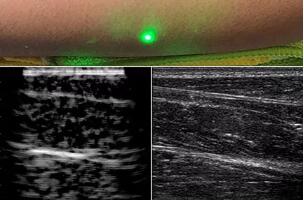

目前,研究人員已經(jīng)與健康的志愿者測試了他們的系統(tǒng):從半米遠處掃描了他們的前臂,并將這些結(jié)果與傳統(tǒng)超聲的結(jié)果進行了比較。他們能夠觀察到深達6厘米的組織,并能看到肌肉,脂肪和骨頭,并報告其結(jié)果可與標準超聲相媲美。

研究人員用一種激光裝置測試了這個想法,該裝置使用一個波長為1,550納米的脈沖激光來產(chǎn)生聲波,并使用第二個連續(xù)激光,調(diào)諧到相同的波長以遠程檢測反射的聲波。第二個激光器是靈敏的運動檢測器,可測量聲波從肌肉,脂肪和其他組織反射回來而引起的皮膚表面振動。反射的聲波產(chǎn)生的皮膚表面運動會導致激光頻率發(fā)生變化,這種變化可以測量。通過機械掃描人體上的激光,科學家可以獲取不同位置的數(shù)據(jù)并生成該區(qū)域的圖像。